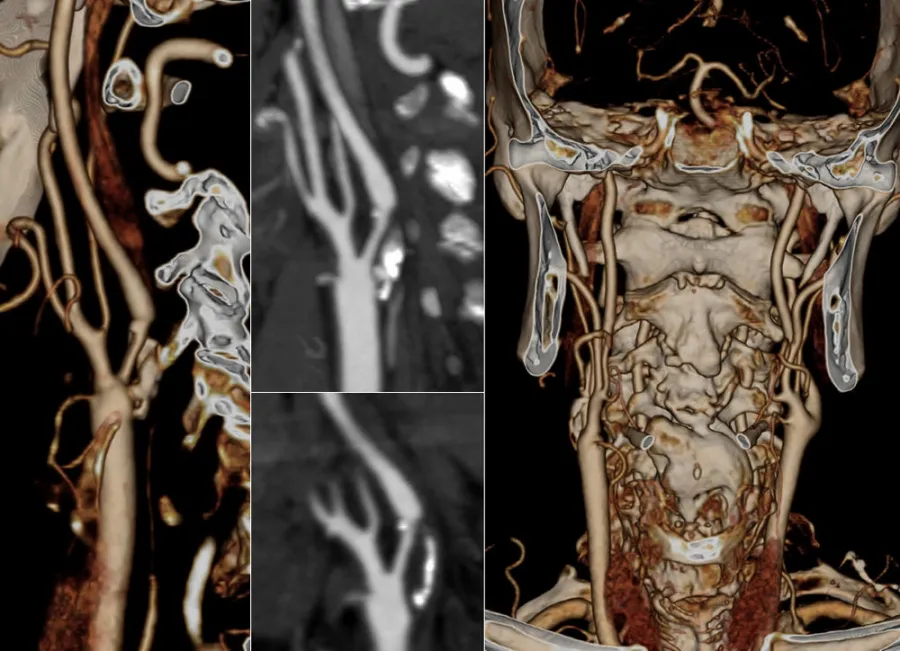

In caso di un restringimento importante delle arterie che portano il sangue al cervello denominate carotidi, in alternativa al tradizionale approccio chirurgico ( TEA o endoarteriectomia carotidea ) in casi selezionati, è possibile intervenire mediante l’introduzione, attraverso un’arteria principale, di un catetere che, posizionato a livello dell’ostruzione, dapprima permette il gonfiaggio di un palloncino che riaprirà il vaso e successivamente consentirà il posizionamento di una speciale maglia metallica ( STENT ) con la funzione di mantenere il vaso aperto nel tempo. Durante la manovra un filtro, posizionato a monte della stenosi, avrà il compito di bloccare e trattenere eventuali impurità che si dovessero generare nel corso della procedura stessa.